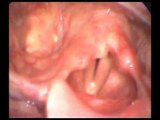

Pourquoi faut il bouger lorsque l'on est suspendu dans son baudrier ?

La pathologie induite par le harnais

Pathologie du harnais